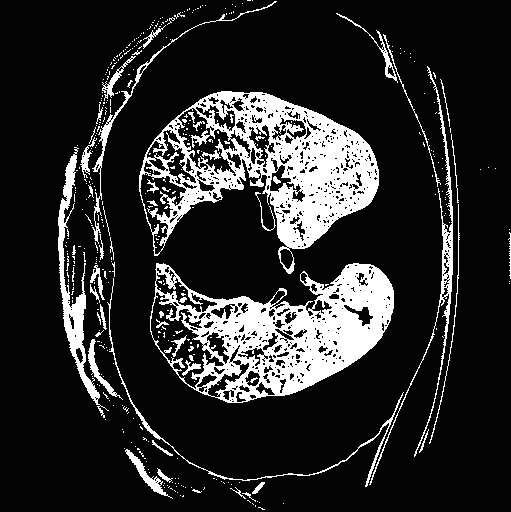

Top row: An image slice demonstrating the lung Isolation process, enacted on a low dose spiral CT scan taken from the LIDC-IDRI database.

- Method Overview: In each CT scan, the internal 3D lung volume was isolated using standard thresholding of pressurevalues ranges associated with lung parenchyma. The remaining voxels were conjoined using a connected components method, implemented through a union-find method, with small and isolated components removed. The remaining gaps were filled in using a standard 3D image closure method. First and second order partial derivatives were computed using Deriche filters, chosen for their stability and suitability in medical image scans. Then, for each of the voxels in the internal volume of the lung the local second order Image Hessian was generated and analyzed for preferred directions using eigenanalysis. This information was then used to weight the contribution of each voxel to standard lung nodule detection methods, to determine if giving stronger weight to voxels with local blob-like shape improved detections results.